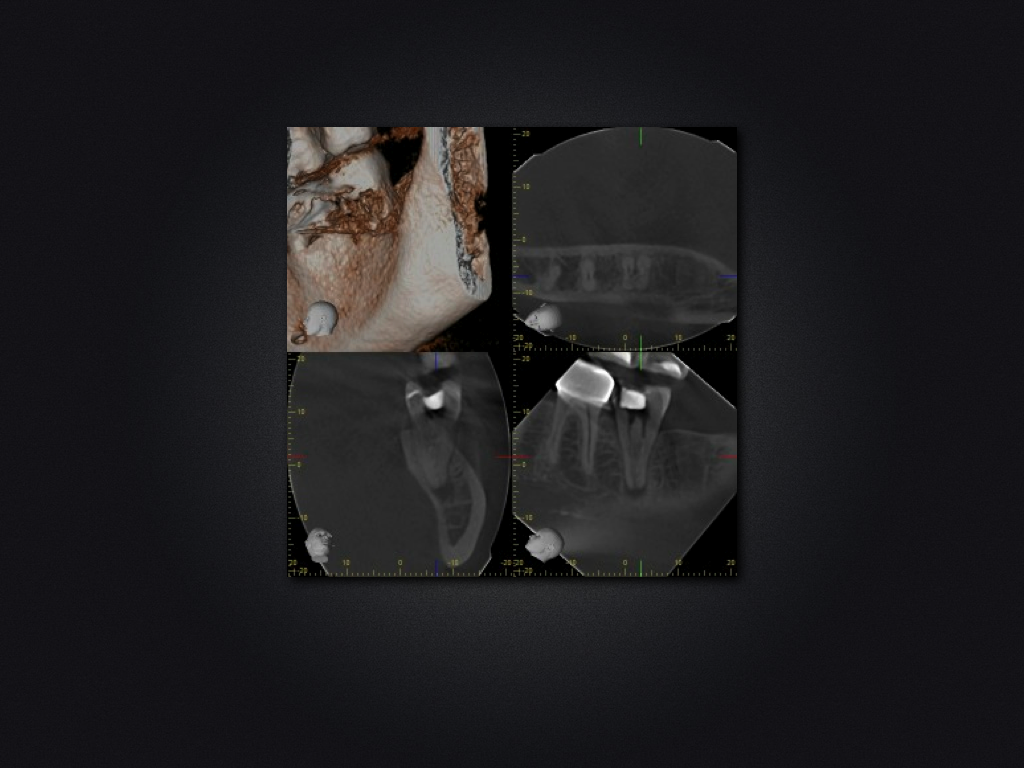

37D.006

1024 × 768

37 c-shaped